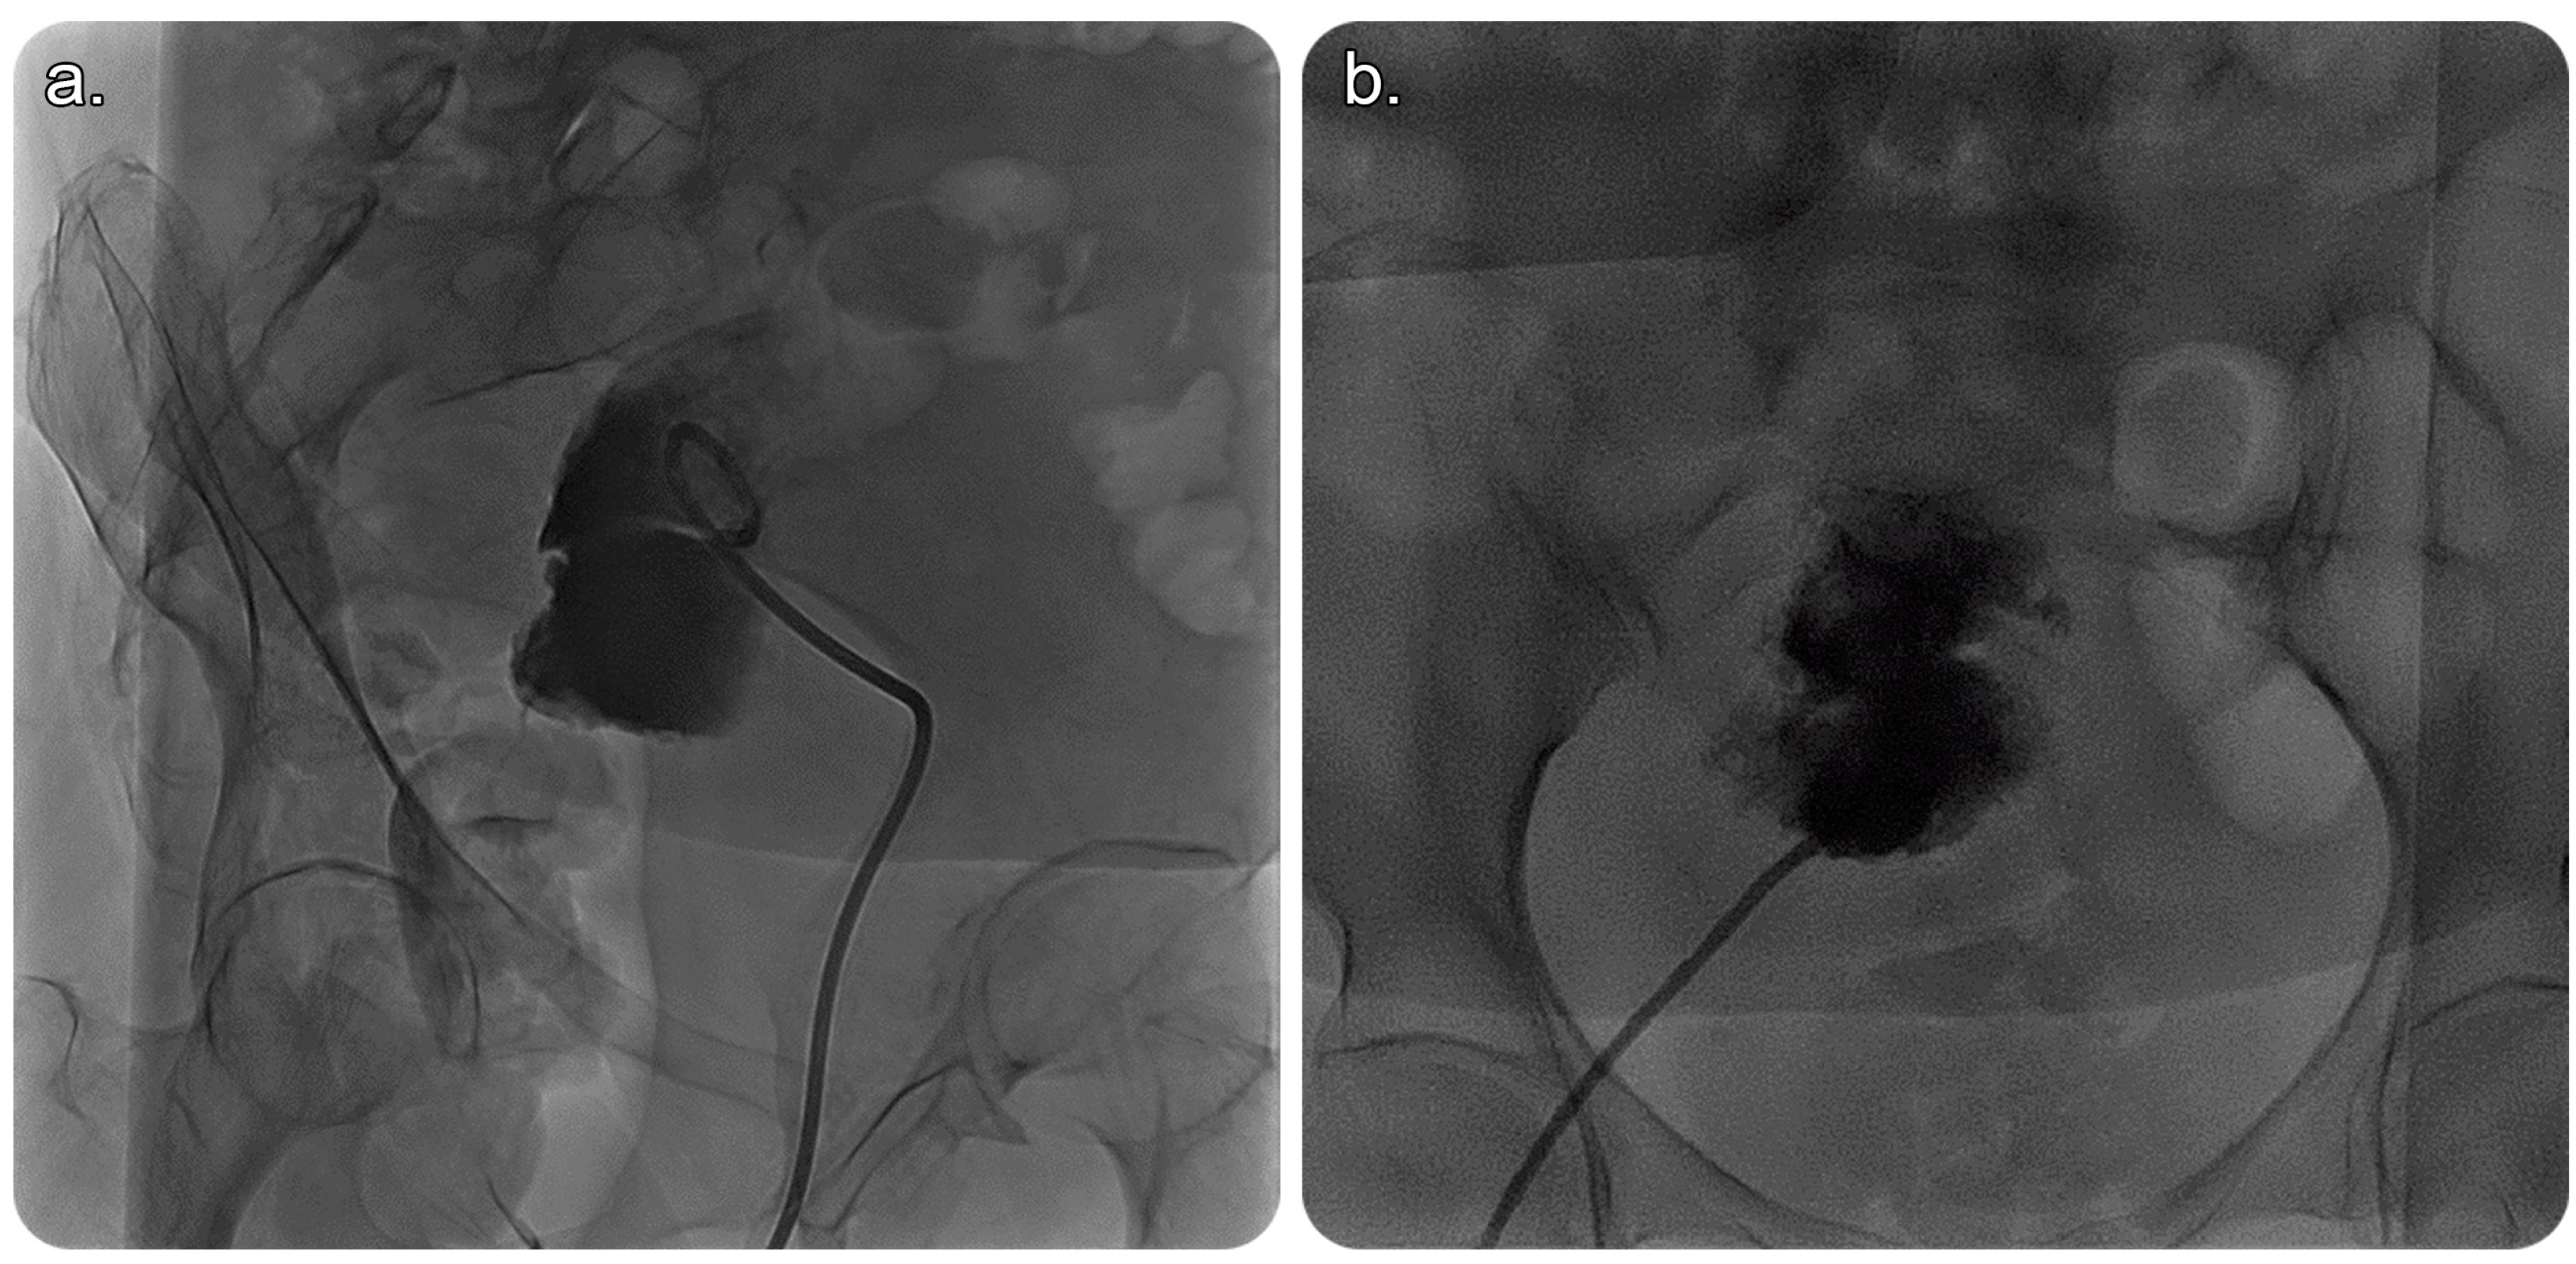

In view of this, the patient was referred to an interventional radiology service for a possible image-guided evacuation of the collection. After obtaining informed consent from the patient and her guardian, we performed an ultrasound-guided percutaneous endometrial drainage of the collection by implementing the dual effects of successive percutaneous retrograde cervical dilation using a non-compliant balloon for stretching the causative cervical stenosis under fluoroscopic guidance; this was followed by retrograde drainage catheter insertion under sonographic guidance in one session (Figure 2 and Figure 3).

Later on, under fluoroscopic guidance and using the same percutaneous retrograde-fashion access, the obstructed cervix was successfully accessed using a 5-French-size angled catheter and wire combination, followed by dilation using a 10 mm diameter by 4 cm length balloon (MUSTANG, Boston Scientific, Marlborough, MA, USA).

Figure 3. (a) Fluoroscopic image of the pelvis in an oblique view showing a 10-French-size pigtail catheter within the endometrial cavity that is filled with contrast material, with no evidence of contrast passage beyond the stenosed/obstructed cervix into the vagina outside the body. (b) Fluoroscopic image (frontal view) showing a 10-French-size pigtail catheter within the endometrial cavity that is filled with contrast with a clear cut-off, which indicates obstruction.

Several approaches can facilitate percutaneous drainage of the endometrial fluid collection, including, but not limited to, the transabdominal, posterior transgluteal, transvaginal, and transrectal catheter insertion routes (Figure 3 and Figure 4). The transvaginal route is commonly used, owing to its proximity to the pelvis [1]. In this case, a percutaneous drainage catheter was used to irrigate the endometrial cavity after cervical dilatation to overcome the obstruction. Drain removal depends on multiple factors, such as minimal or no drain, improvement based on imaging, or a decrease in inflammatory markers [1].